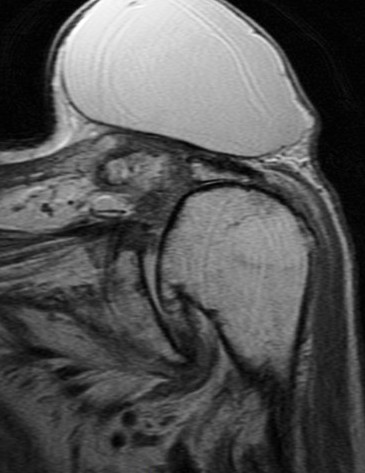

74 y/o female with mass on shoulder. Also pain. Evaluate mass and r/o rotator cuff tear.

Large cyst associated with a rotator cuff tear and AC arthrosis. Geyser phenomenon if communication shown at arthrography (some definitions specify arthrography). This was not an arthrogram. Patient also has a chronic rotator cuff tear. Reference article.

Large cyst above a degenerated acromioclavicular joint ( RID1895 )